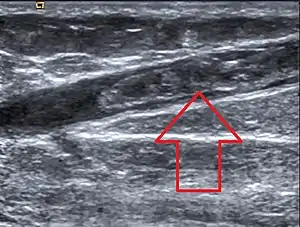

Ultrasonographic image showing thrombosis of the great saphenous vein. | |